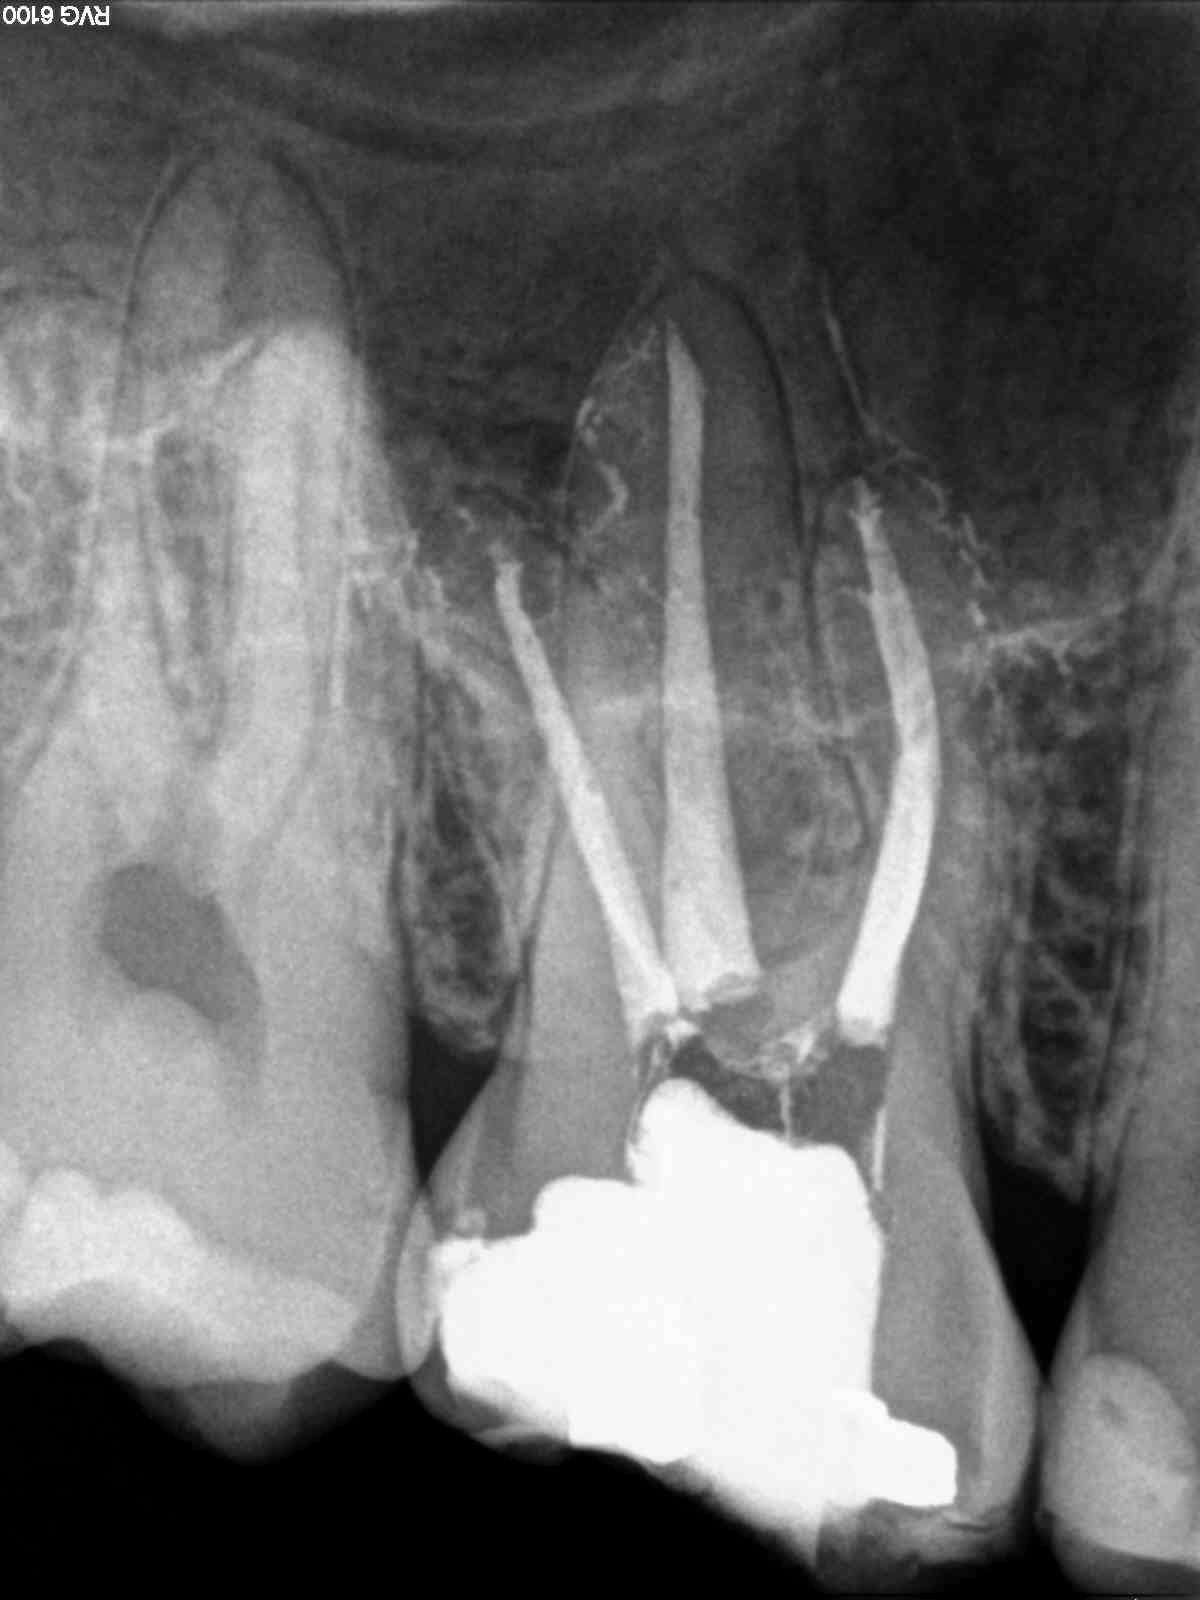

B) Un 1.6 con una pulpitis irreversible.

B)